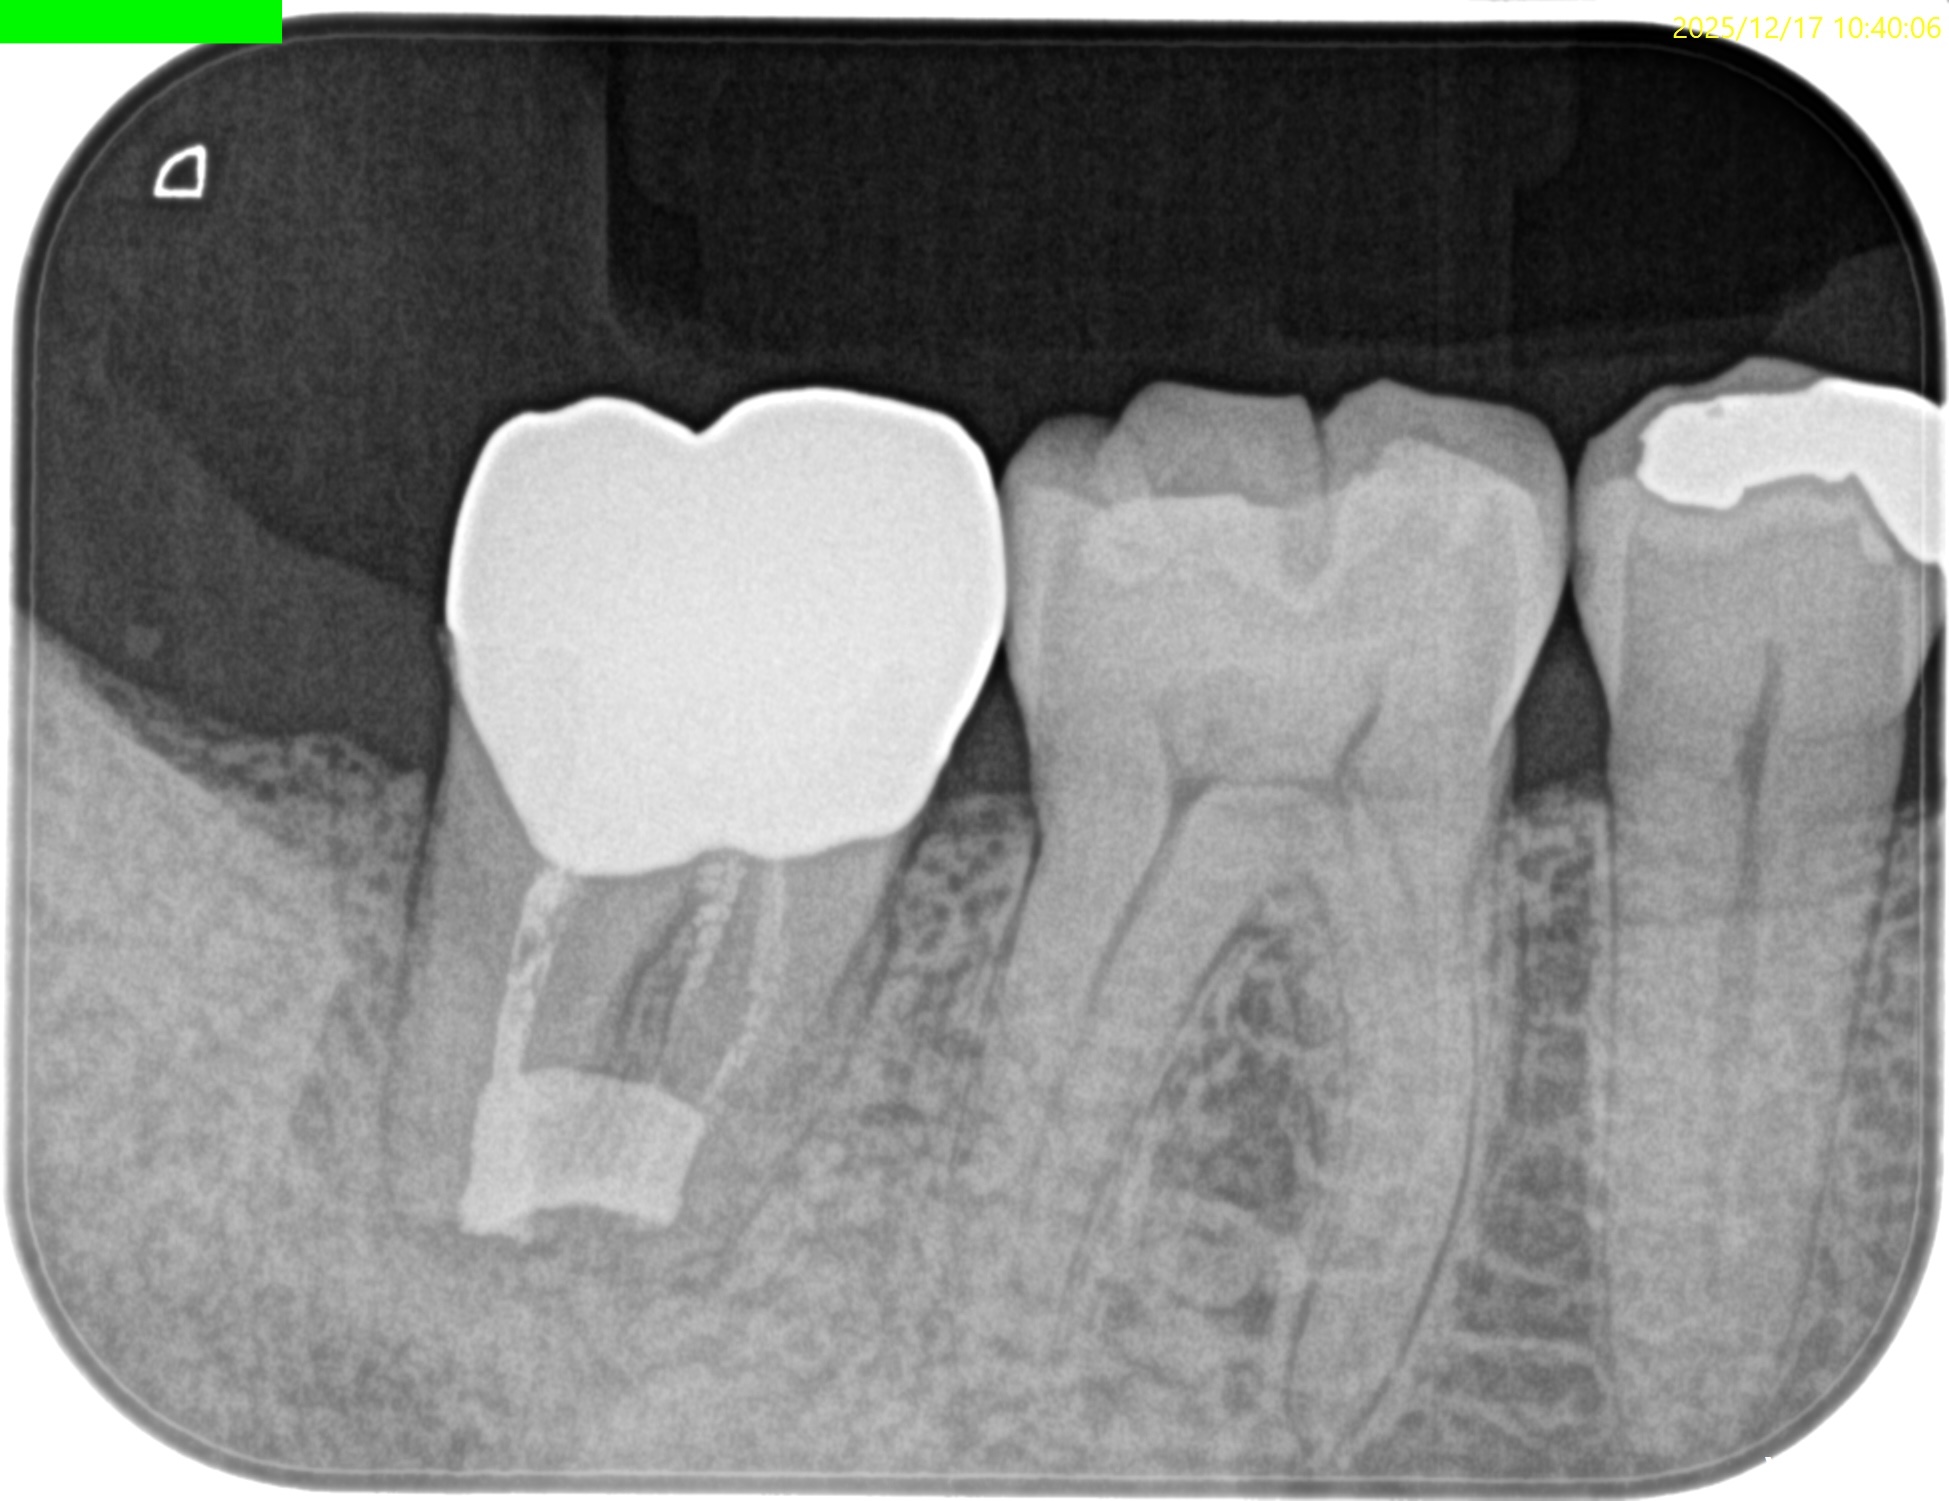

PA所見も半年前とは大違いである。

Sinus tractは消失し歯槽骨も大幅に回復し、最終補綴も装着されている。